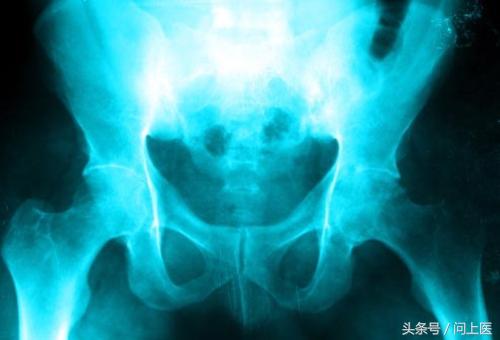

12 / 24 其他并发症

一些溃疡性结肠炎患者也会有骨质疏松症、关节炎、肾结石,以及眼部疾病(如葡萄膜炎),极少数情况下也会有肝脏疾病。研究表明这些并发症是由于免疫系统触发了广泛的炎性反应。使用抗炎药物治疗溃疡性结肠炎可能会改善这些并发症。